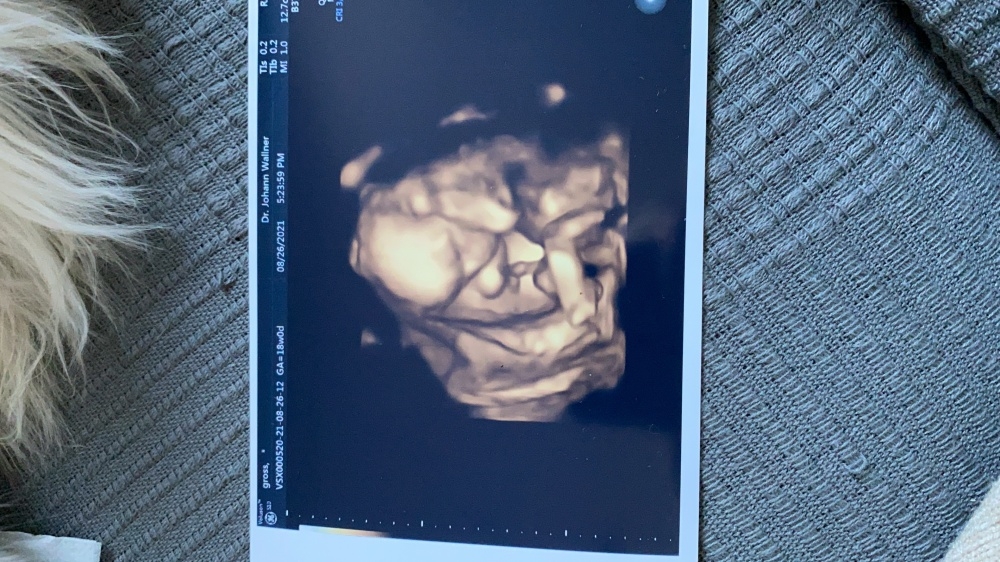

Zwergi geht es gut er hat auch gleich die Mukipass Untersuchung vorverlegt um 2 Wochen. hab dann gestern mein 1 3D Bild bekommen und er hat auch gesagt er glaubt er kann schon sagen was mein zwerglein wird. aber ich mach mir jetzt noch in Krankenhaus einen Termin fürs Organscreening aus ich glaub da steht es dann zu 💯 fest was mein bauchbewohner wird in der 22 Ssw ca

Zwergi geht es gut er hat auch gleich die Mukipass Untersuchung vorverlegt um 2 Wochen. hab dann gestern mein 1 3D Bild bekommen und er hat auch gesagt er glaubt er kann schon sagen was mein zwerglein wird. aber ich mach mir jetzt noch in Krankenhaus einen Termin fürs Organscreening aus ich glaub da steht es dann zu 💯 fest was mein bauchbewohner wird